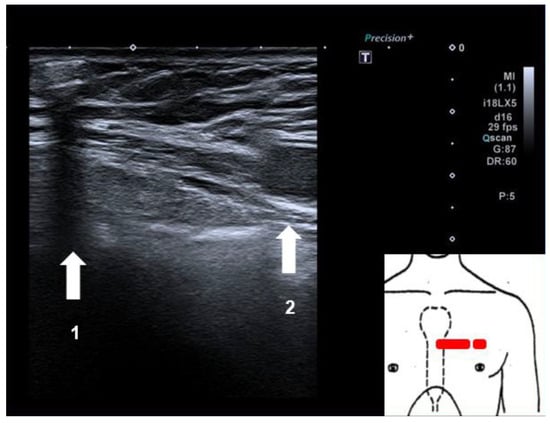

After defining a sterile field and disinfecting the local area, ultrasound-guided subcutaneous local anaesthesia was performed, in the direction of the planned implantation orientation of the device (parallel to the left sternal boarder, caudally, starting in the fourth intercostal space). After this, we inserted the device with ultrasound guidance in the direction in which the local anaesthetic was administered, following the manufacturers recommendations on how to implant their device. A sonographic check showed that there was sufficient subcutaneous tissue between the loop recorder and the medial boarder of the left silicone implant (Figure 2). The initial device interrogation revealed a sensing level of more than 0.3 mV (lying and sitting positions) with a clearly visible P-wave and good discrimination of the QRS-complex (Figure 3). The patient was discharged after a few minutes of clinical observation with normal vital signs and no specific complaints.

Figure 2. Sonographic check of the device position in relation to the silicone breast implant: 1. Subcutaneous ILR with posterior ultrasound shadow. 2. Medial boarder of left silicone breast implant.